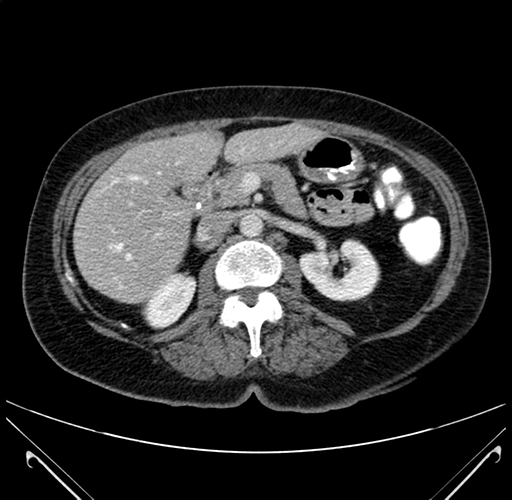

Pre-Chemo: Axial Venous

Imaging analysis

Based on your CT findings, which issue(s) would give reason for "planned slowing down moment(s)" in this case?

Considering a standard right hepatectomy procedure, what step(s) of the operation would you do differently in this case?